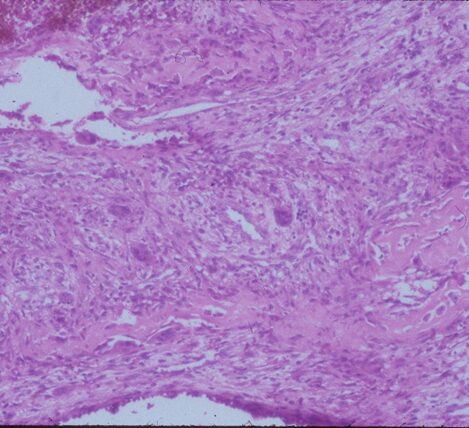

Microscopic Pathology

- Hemorrhagic tissue with large cavitary spaces divided by septum of spindle fibroblastic cells, inflammatory cells and few giant cells.

- Osteoid formation could be noted (reactive and benign in nature)

Fig 3 a,b,c. Microscopic pathology of an Aneurysmal Bone Cyst (ABC):